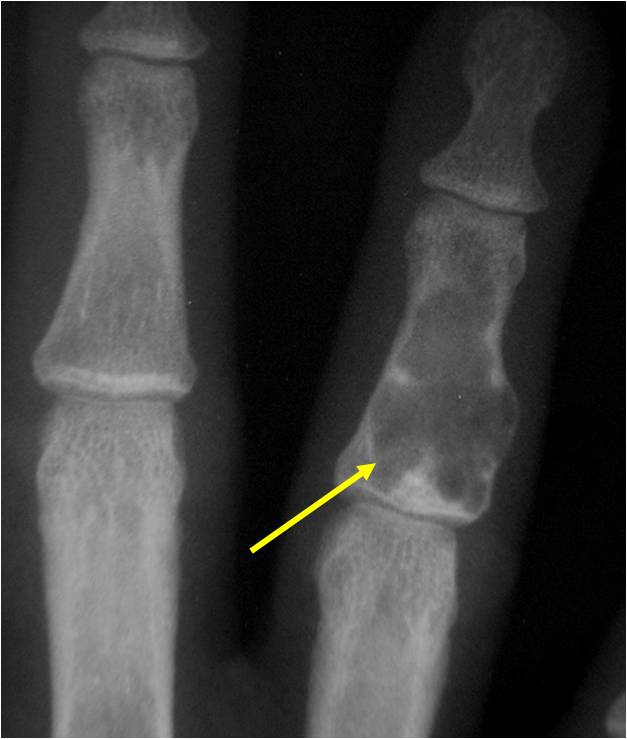

Geographic Lesion Bony Expansion Minimal Calcification Some Enchondromas do not calcify

Geographic lesion, Stippled calcifications in lesion, Phalanx is expanded, Significant endosteal scalloping, No cortical destruction, No soft tissue extension, Cortex Scalloped and Expanded